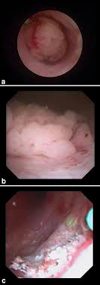

Los tumores de vejiga son lesiones que requieren extirpación, el método más habitual es la resección endoscópica mediante energía monopolar o bipolar, lo cual permite la extirpación en fragmentos del tumor para realizar el estudio anatomopatológico e identificar el tipo de lesión y profundidad de la misma. Recientemente se está estudiando un tipo de resección diferente denominada resección en bloque, con lo cual se extirpa todo el tumor en su totalidad y no en fragmentos, con lo que se consigue un análisis más certero de la pieza quirúrgica, siendo una de las herramientas estudiadas el láser, con lo cual se puede conseguir la extirpación en bloque antes mencionada, sin embargo este procedimiento aún está en estudio, por lo cual aún no está estandarizado.